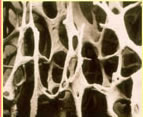

骨質疏鬆只要用量不超過個體生理需求量,就不會出現副作用。其副作用類似於維生素D3過量的症狀,即高血鈣症綜合徵或鈣中毒。